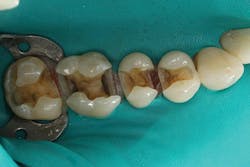

Figure 2: Hygienic nonlatex rubber-dam isolation was established; the existing amalgam restorations and decay were removed; and the preparations were refined, cleaned, and disinfected.

Figure 3: A segmented matrix setup with two Composi-Tight 3D-XR rings (Garrison Dental Solutions) and a 5.5-mm Slick Band (Garrison Dental Solutions) was placed on No. 3. Then, the preparation enamel was selectively etched with 37% phosphoric acid etchant with benzalkonium chloride (Bisco) for 20 seconds.

Figure 4: A universal adhesive was scrubbed for 20 seconds, air thinned, and light cured for 10 seconds. A layer of Tetric EvoFlow Bulk Fill was placed up to the proximal box and to the pulpal floor, then light cured for 10 seconds. After light curing, the bulk-fill composite exhibited a dentinlike opacity, helping to mask the discolored dentin.